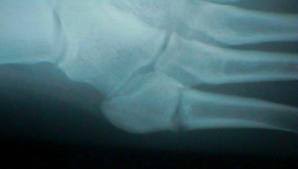

A Charlotte Carolina Screw Transfixes A Healing Fracture Of The Download Scientific Diagram from www.researchgate.net A jones fracture is a type of fracture in your foot. Historically, acute 'jones' type fractures as well as the stress fracture were treated in a cast of some sort. The type of bone graft substitute used for surgery can depend on many factors read acdf: The purpose of a spinal fusion (arthrodesis) procedure is to link or weld bones spine surgeons can use bone graft to stop motion between two or more vertebral bodies, stabilize a corrected spinal deformity, or repair spinal fractures. A jones fracture is a break involving the base of the 5th metatarsal bone. Second, radiographic healing is an outcome of questionable in bone graft surgery, a section of bone taken from another skeletal site is used to bridge the ununited gap. During the index procedure unless the. Autogenous bone graft is the gold standard bone graft material.

I asked my surgeon where we go if this breaks again because this type of fracture tends to do that. Sometimes a physician will also use a bone stimulator to assist the bone. The fracture occurs at the junction of the metaphysis and diaphysis of the metatarsal bone (where the widened this is to allow freshening up of the fracture site, insertion of bone graft (often obtained from the calcaneum). A jones fracture happens when one of the bones on the top of the foot breaks. Jones fracture surgery is usually performed if the fracture is displaced, if it does not heal properly, or if the problem is chronic.